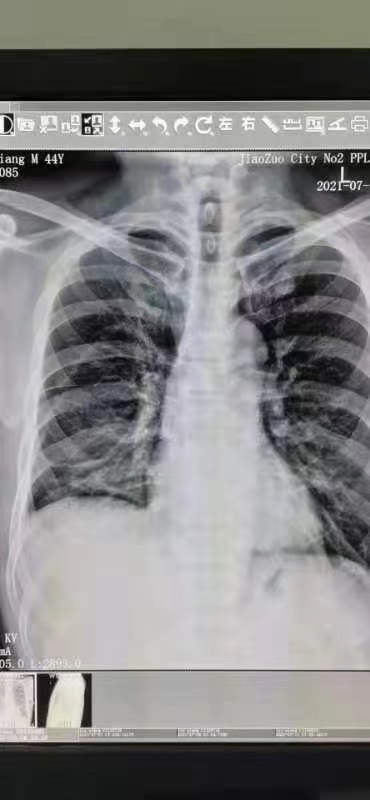

2021年7月13日 患者家属求诊,并提供医院7月6日检查报告、医院治疗后7月11日第一次复查报告

病例报告显示右侧胸腔及叶间积液,右肺膨胀不全,左肺病变,左侧胸膜增厚,肝脏异常强化灶,可能血管瘤,同时肝脏还有小囊肿、右肺下叶病变。患者年龄不大,但自身有很多基础疾病。

右侧胸腔及叶间积液,右肺膨胀不全,右肺病变,

右侧淋巴开始轻度肿大,同时左肺开始慢性炎症,左侧胸膜增厚 。

7月22日的CT检查报告,相比上次的密密麻麻一堆,最后诊断只有二句:两侧胸膜黏连;右侧可能积液,消除后留下巨大水坑。基本上无多大问题。